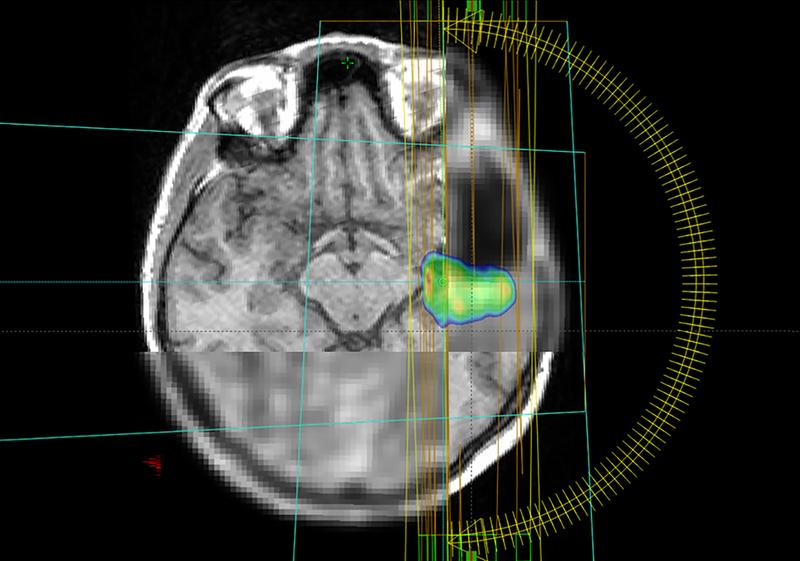

Aggressive Hirntumore dank innovativer Bildgebung und KI präzise bestrahlen

Mit 1,2 Millionen Euro fördert die Europäische Union ein internationales Projekt unter Leitung des Universitätsklinikums Freiburg zur Bestrahlung gefährlicher Hirntumore / Kombination von PET- und MRT-Bildgebung soll mit Künstlicher Intelligenz ausgewertet werden. Glioblastome sind seltene, aber besonders aggressive Hirntumore. Häufig werden sie mit einer Strahlentherapie behandelt. Ein internationales Forschungsteam unter Leitung des Universitätsklinikums Freiburg untersucht nun in der Studie MATTO-GBM, wie der Tumor mit maximaler Intensität bestrahlt und umliegendes, gesundes Gewebe geschont werden kann. Dabei setzen die Forschenden auf eine…